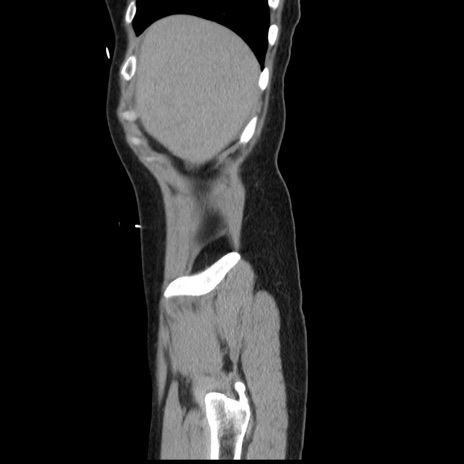

横断像

【症例】 50歳代女性

【主訴】 腹痛

【現病歴】前日生レバーを食べた。今朝に排便あり。 昼前に突然発症の腹痛を生じ、当院救急外来を受診した。

【既往歴】 子宮筋腫にてで子宮全摘後

【身体所見】 意識清明、腹部:平坦、軟、下腹部やや左を中心に圧痛・反跳痛あり、筋性防御あり

【データ】WBC 7800、CRP 0.07